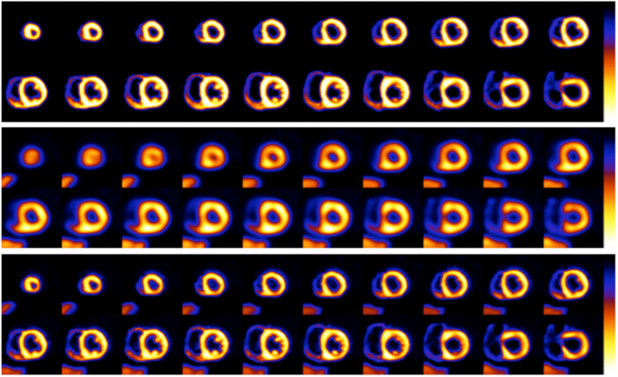

3.2. Application of PVC in cardiology

As mentioned in the introduction, quantification of the three-dimensional distribution of a radioactive tracer is hampered by the limited spatial resolution of PET and SPECT imaging systems. Furthermore, it should also be obvious that most disease states start small, and early detection influences the treatment options as well as the outcome. Imaging of the heart as a whole suffers from partial volume effects. The myocardial wall of the left ventricle (LV) is normally 0.8–1.2 cm thick, varying in thickness with location (thinner at apex, thicker where papillary muscles are located), while thickness and wall position both change with cardiac contraction. So the partial volume effects are not only position dependent but also time dependent. This is further confounded by respiratory motion. ROC analysis (Narayanan et al 2003) showed the incremental diagnostic value of correcting for attenuation, Compton scatter and resolution effects in perfusion SPECT. In a follow-up investigation, Pretorius et al (2005) showed that stress perfusion SPECT with iterative reconstruction including compensation for all physical effects (attenuation, scatter, and resolution) was equivalent or better than FBP, even when the FBP studies were read with all the extra clinical nuclear medicine imaging information available (including both stress and rest gated planar and SPECT images and polar maps as well as knowledge of patient gender). Equivalency was shown to exist in the right coronary artery (RCA) territory where spill-over from the liver or bowel could mask perfusion defects (Pretorius and King 2008).